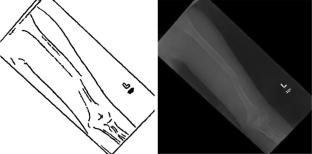

Fig. 1

Fig. 2